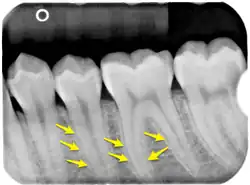

Radiological appearance

The lamina dura is a dense bone structure visible on dental radiographs as a thin, radiopaque border adjacent to the periodontal ligament and alveolar crest, forming part of the tooth socket.[10][11] Its role as "bundle bone" stems from its dense composition containing Sharpey's fibers, which develops during tooth formation as an egg-shell-like envelope and persists after eruption as a radiopaque layer.[10][8] Rather than being a radiographic artifact, studies confirm its appearance is determined by both structural properties and X-ray beam direction.[12][8] Several factors influence its radiographic visibility, including tooth position, root number, condition of the periodontal ligament, X-ray beam angulation,[13] anatomical structure superimposition, and film exposure times.[14] These variables can cause irregular appearances or apparent discontinuity, particularly in maxillary molars and premolars. Proper X-ray angulation, allowing rays to pass tangentially through the structure, enhances its visibility, while improper alignment or altered anatomy can obscure its appearance.[8][13]